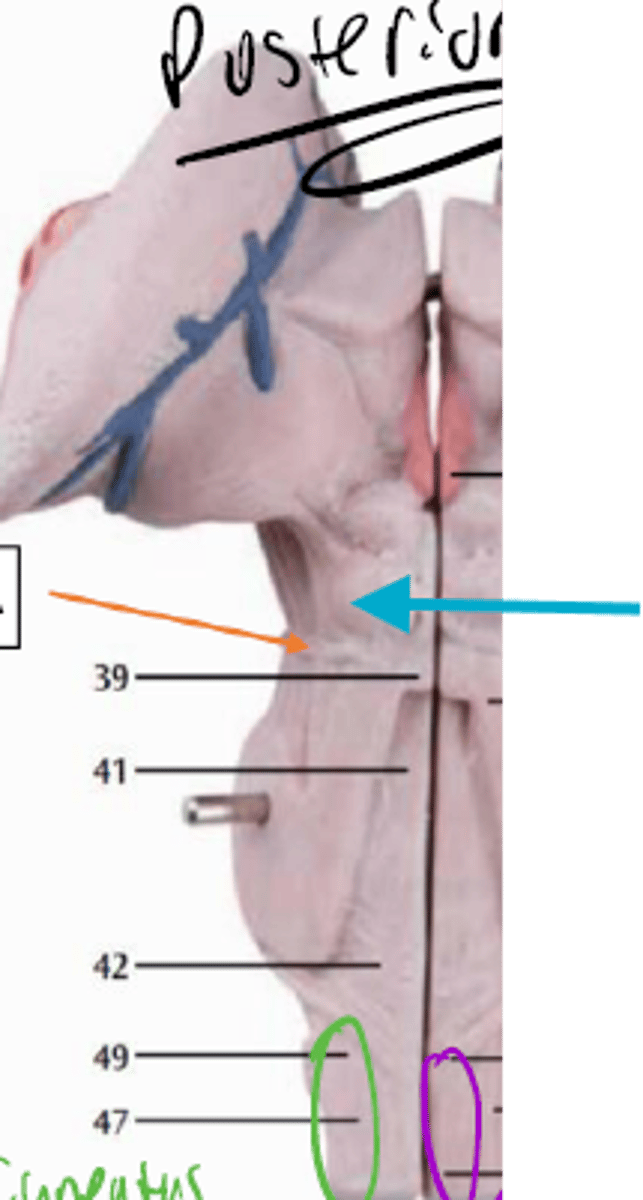

What is the blue arrow pointing at?

What space is the yellow arrow pointing to?

What part is the yellow arrow pointing to?

what space is the yellow arrows pointing to?

what is the blue arrow pointing to?

what structure is the blue pin in?

What is number 50 or the blue dot?

blue arrow is pointing to which structure?

The area the blue arrow is pointing to?

structure blue arrows are pointing to?

What area is the orange structure pointing to?

What area is the blue arrow pointing to?

Where is the yellow arrow pointing to?